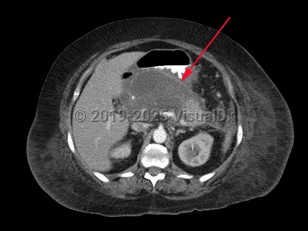

Pancreatic pseudocyst

A pancreatic pseudocyst is a localized, mature, fluid-filled collection, sometimes with debris, located outside of the pancreas. It has a nonepithelialized wall of fibrous and granulation tissue, with no necrosis present. Pancreatic pseudocysts typically appear at least 4 weeks after an episode of acute pancreatitis or blunt or penetrating pancreatic trauma. Pancreatic pseudocysts can also form in patients with chronic pancreatitis if there is an acute exacerbation of the underlying pancreatitis. Ten percent of patients with chronic pancreatitis will develop pseudocysts. Pancreatic pseudocysts are more commonly diagnosed in males.

Most cases of pancreatic pseudocyst resolve without intervention, but they may produce a wide range of signs, symptoms, and clinical manifestations. These may include abdominal mass, abdominal pain, fever, chills, and jaundice.

Complications may include duodenal obstruction or biliary obstruction due to pseudocyst expansion, fistula formation into adjacent viscera including the peritoneal, pericardial, and pleural cavities, spontaneous pseudocyst infection, and pseudoaneurysm.